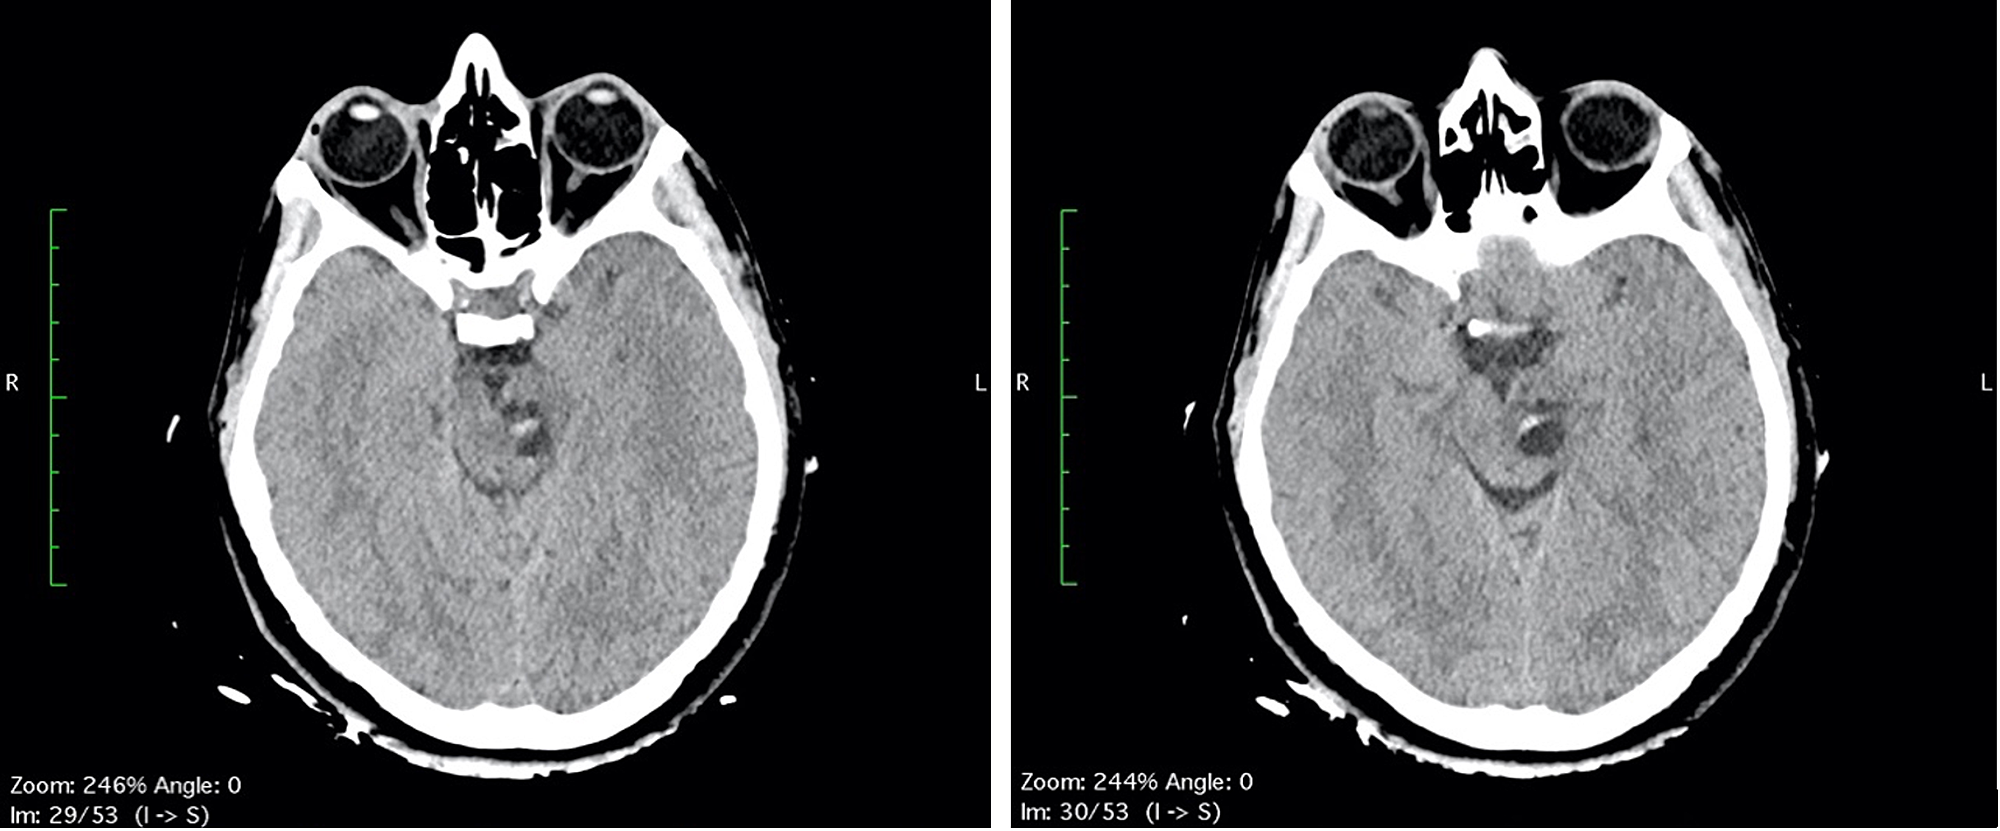

The first day after surgery, the patient was transfunded for hemoglobin 6.8 g/dL (normal range 12-16 g/dL), referring to scalp surgery. She complained headache, vertigo, nausea and diplopia, reflecting an involvement of the brainstem and the oculomotor nerves. A second CT and brain MRI with IV contrast were performed: CT scan showed a fluid-fluid level, with enlargement of left cerebral peduncle and a slight mass effect (Figure 2). MRI scan confirmed the same findings of fluid-fluid level, with enlargement of left cerebral peduncle and a slight mass effect; no contrast enhancement was observed: these findings were referred to enlargement of VRSs with post-traumatic bleeding. Neither SAH nor intracerebral hematomas were revealed (Figure 3). No neurosurgery was indicated but only clinical and imaging follow up.